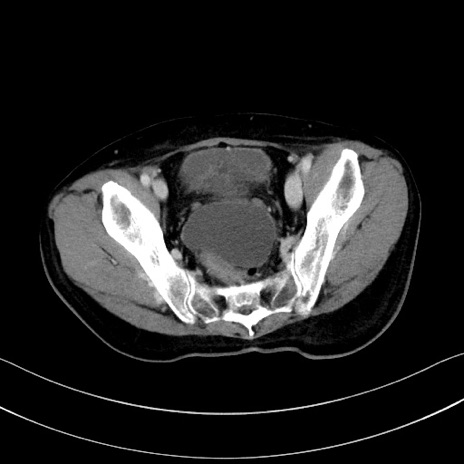

症例28(横断像)

【症例】60歳代男性

【主訴】嘔吐

【現病歴】胃癌にて胃全摘後。食思不振が悪化し、夜中に嘔吐することがある。

【既往歴】胃癌、胃全摘、脾摘、胆摘後

【データ】WBC 5900、CRP 10.56